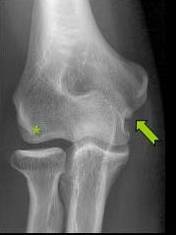

COMPRESIUNEA NERVULUI ULNAR PRIN OSTEOCONDROM SECUNDAR

Parestezii in teritoriul nervului ulnar Mica osificare →in contact cu n. Ulnar → Pe IRM mica lacuna osteocondrala a condilului →* corespunzator locului de plecare a osteocondromului